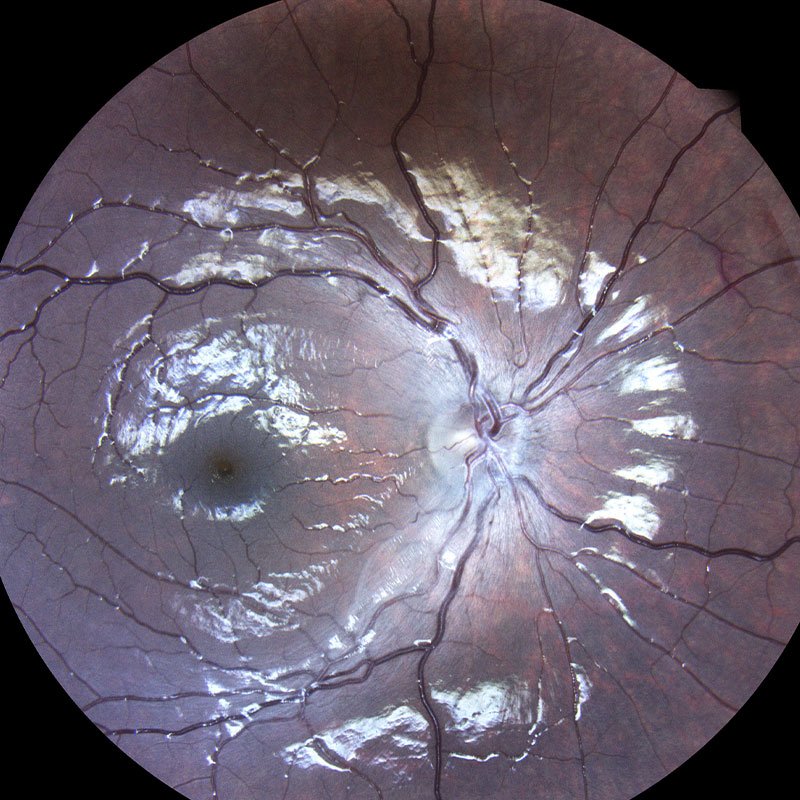

Η συγγενής φυλοσύνδετη ρετινόσχιση είναι μια κληρονομούμενη δυστροφία του αμφιβληστροειδή η οποία οφείλεται σε μεταλλάξεις του γονιδίου RS1. Εμφανίζεται με μείωση της κεντρικής όρασης σε νεαρούς άρρενες. Ο ηλεκτροφυσιολογικός έλεγχος (Ηλεκτροαμφιβληστροειδογράφημα) είναι πολύτιμος για τη διάγνωση της νόσου μιας και έχει χαρακτηριστικά ευρήματα στις καταγραφές ενώ ο γενετικός έλεγχος ταυτοποιεί τη διάγνωση.